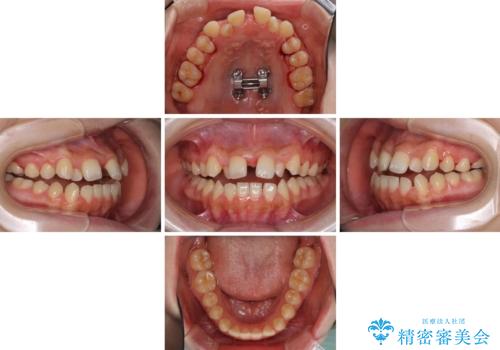

- 前歯のデコボコと、下顎の変位と受け口を気にして来院された患者様です。

初診時には大学病院にて顎の骨を切る外科矯正を勧めましたが、妥協的なゴールでも構わないので外科処置をせずに矯正を行いたいとのことでした。

まずは急速拡大装置にて上顎骨を側方に拡大し、インビザラインにて歯列と咬合を整えることとしました。

インビザラインでの治療が困難な場合には、ワイヤー矯正にて仕上げる可能性があることを予めご了承いただきました。